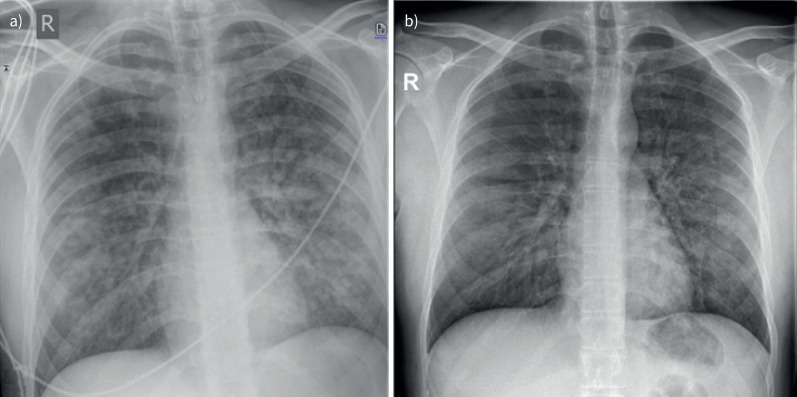

负压性肺水肿是术后患者急性呼吸窘迫的一个未被充分认识的原因。表现包括急性肺水肿和可能的DAH。及时认识和干预至关重要。https://bit.ly/4jYzOmn。

Negative pressure pulmonary oedema is an under-recognised cause of acute respiratory distress in post-operative patients. Presentations include acute pulmonary oedema and possibly DAH. Prompt recognition and intervention are essential. https://bit.ly/4jYzOmn.